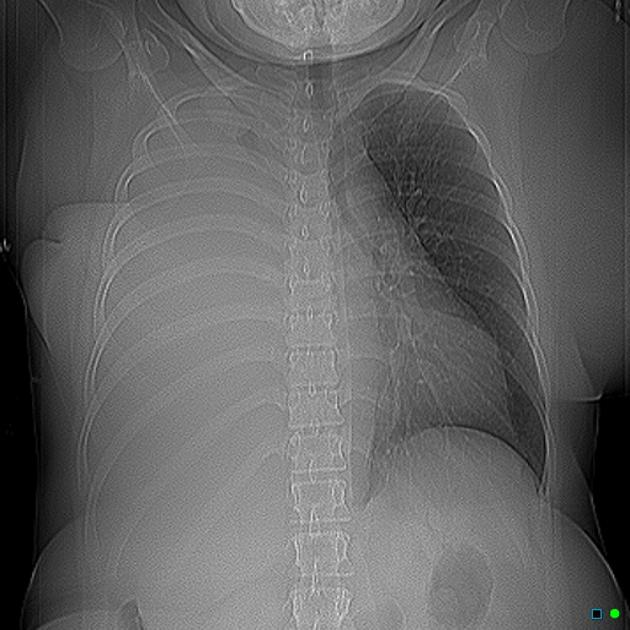

White Out

Pneumonia